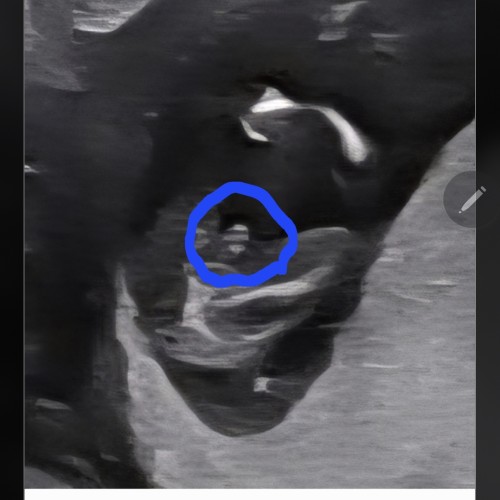

6주0일 초음파

난황이 안보이는 시기인가요?! ㅎㅎ 아니몀 병원마다 봐주시는 각...